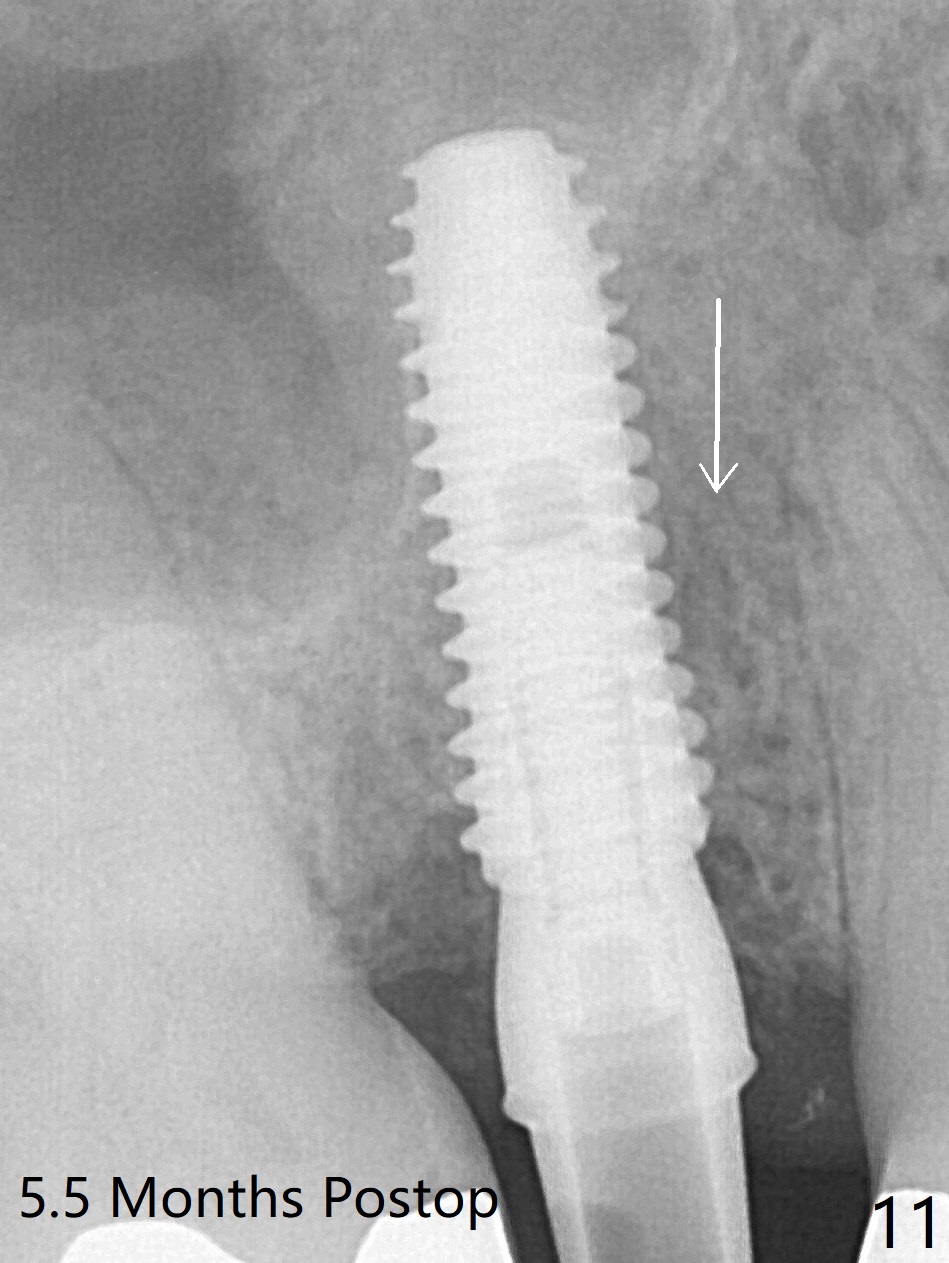

The 48-year-old man agrees to extract the tooth #4 with buccal and palatal fistulae (Fig.1,2 >) and large PARL (Fig.3 *) because of purulent discharge. The large post (Fig.3 P) is most likely associated with a longitudinal fracture. The latter is not noted until postop (Fig.4 <). Intraop finding is large amount of granulation tissue removed from the mesial apical region (Fig.3,5 *). With 10.5 mm offset, Sinus Approach Drill (19 mm) is estimated too short for sinus lift after 3x8.5 mm drill. Without careful repeated check, 2.2x10 and 2.2x11.5 mm drills are used. The sinus floor is perforated, but the membrane seems to be intact. The perforation is too small to insert PRF, but alright for allograft. Then nose blowing test shows that the sinus membrane is perforated, which seems to be repaired after placement of 2 pieces of PRF membrane, followed by another round of allograft (Fig.5 G), which is lifted by a 4x10 mm IS dummy implant. Before placement of a 4.5x11.5 mm final UF implant, allograft is placed in the 3 defective bony areas mentioned above, including the apical mesial one (Fig.6 *). But the final UF implant seems too short with non-satisfactory torque. The latter appears to be solved with the increased length of the implant (Fig.7). The gingiva around the provisional (P) is healthy without fistulae buccal (Fig.8) or palatal 17 days postop (Fig.9). A new abutment with 1 mm longer cuff is seated completely 5.5 months postop (Fig.10 < (no gap), as compared to Fig.7). The lower portion of the mesial defect seems to have been repaired (Fig.11 arrow, as compared to Fig.7). The bone in the sinus seems stable 1.5 years postop (Fig.12). There is no crestal bone loss 4 months post cementation (Fig.13). Return to Upper Premolar Immediate Implant, Trajectory II Xin Wei, DDS, PhD, MS 1st edition 09/27/2019, last revision 04/12/2021